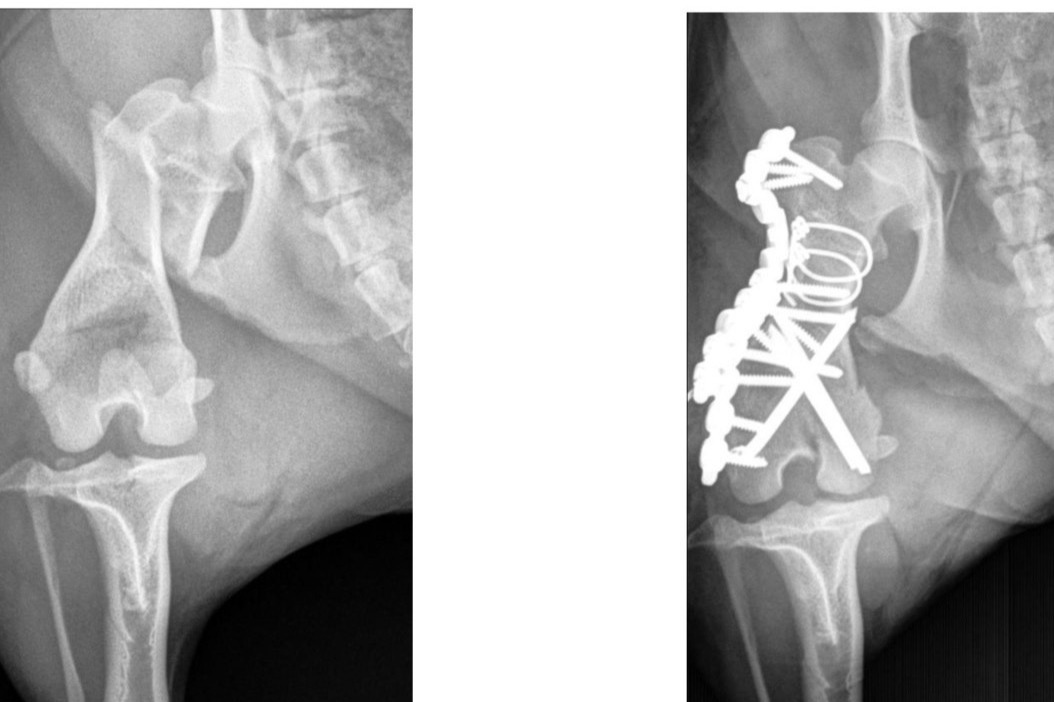

...But last week, a squirrel must have caught her eye because she unexpectedly jumped out the window. She took a pretty hard fall and ended up fracturing her femur in multiple places, requiring emergency surgery.